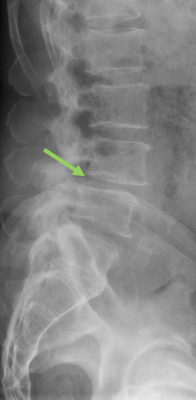

Spondylolisthese - Wirbelgleiten

Von einem Wirbelgleiten spricht man bei Verschiebung bzw. Verkippung zweier benachbarter Wirbelkörper gegeneinander. Eine Retrolisthese bezeichnet das Verschieben des kopfnäheren Wirbelkörpers gegenüber dem darunterliegenden Wirbelkörper nach hinten, analog wird das Gleiten des Wirbelkörpers nach vorn als Anterolisthese bezeichnet. Zu unterscheiden ist zwischen einem frühkindlich erworbenen Wirbelgleiten mit vorliegender Defektsituation im Zwischenwirbelbereich des Wirbelbogens (sog. Spondylolyse) und einem verschleißbedingten, degenerativen Wirbelgleiten mit intakten knöchernen Strukturen und begleitender Arthrose der kleinen Wirbelgelenke sowie Insuffizienz der Bandstrukturen.